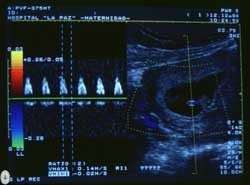

Dentro de las ecografías se puede añadir la técnica doppler, que se utiliza para medir y evaluar el flujo de sangre que circula a través del sistema circulatorio y del corazón del bebé y sobre todo de las arterias umbilicales que son las que proporcionan oxígeno al feto. Está indicado en embarazo de alto riesgo. Mide el grado sufrimiento fetal.